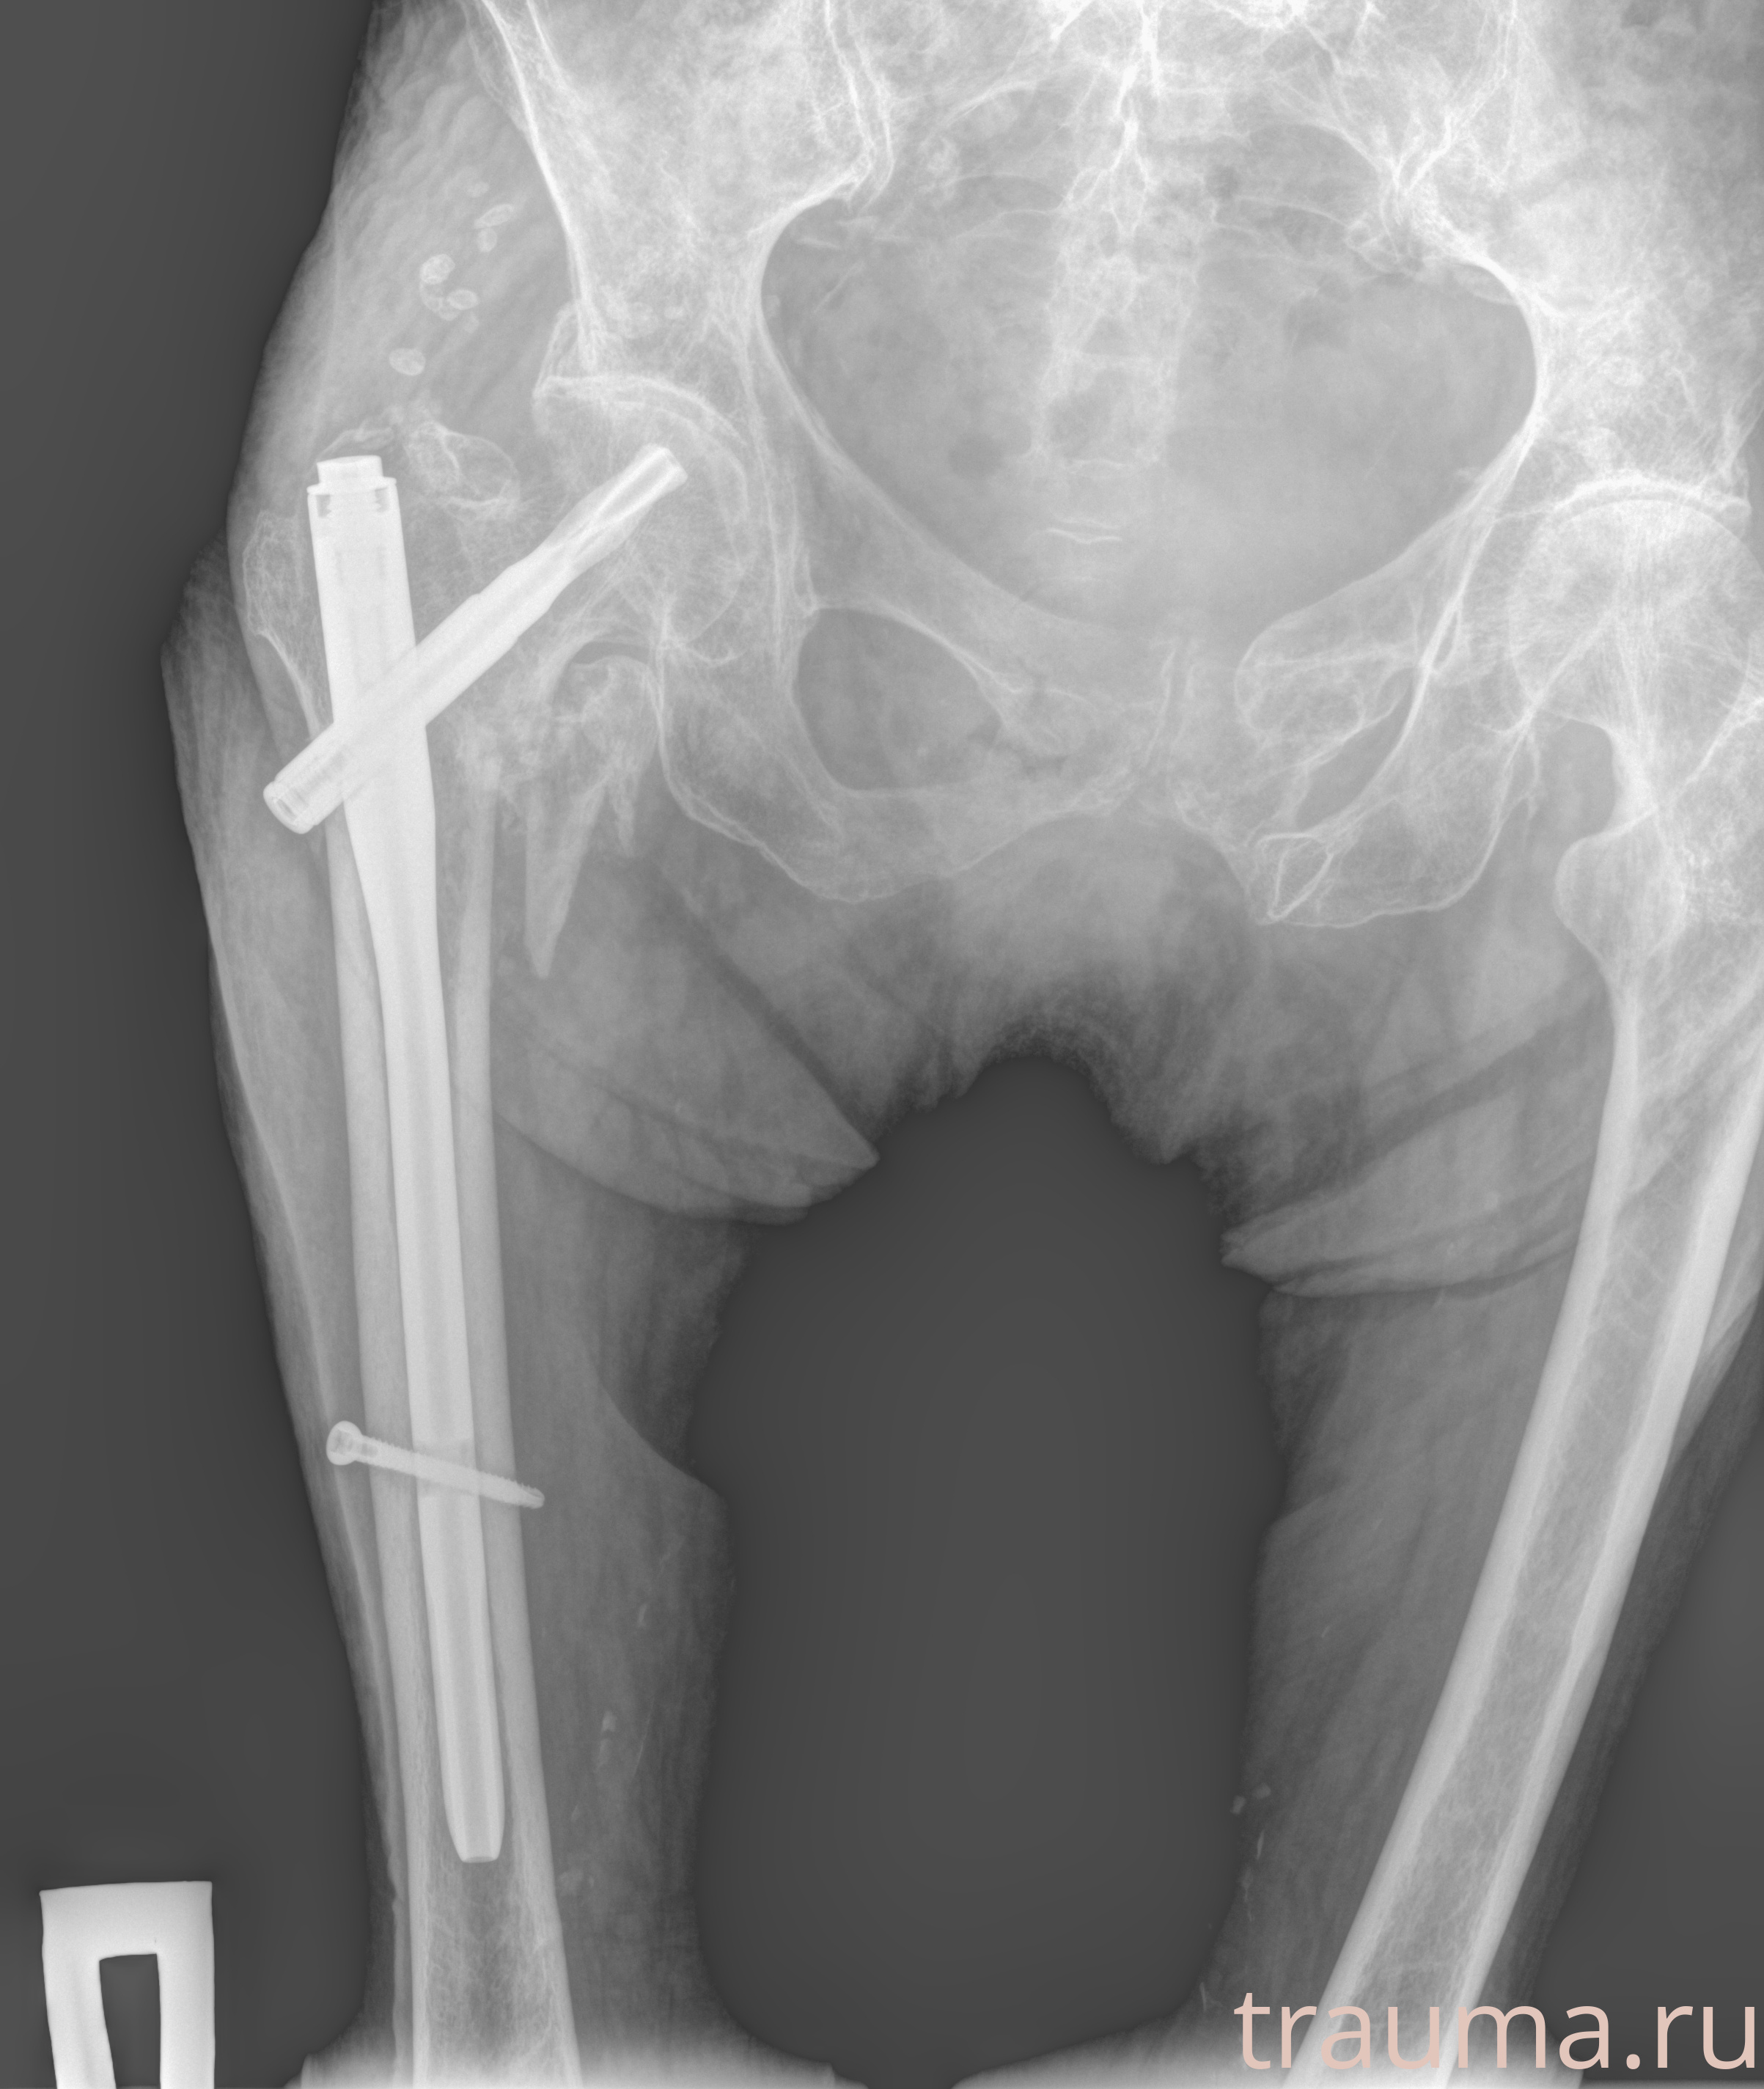

Рентгенограммы

Рентген на дому: по вашему адресу приезжает врач-рентгенолог, травматолог-ортопед с мобильным рентгеновским аппаратом, проводит диагностику травмы или заболевания, делает необходимые рентгенограммы, дает рекомендации по дальнейшему лечению. Получить качественные снимки в домашних условиях возможно благодаря уникальной методике, разработанной МосРентген Центром для института  Склифосовского